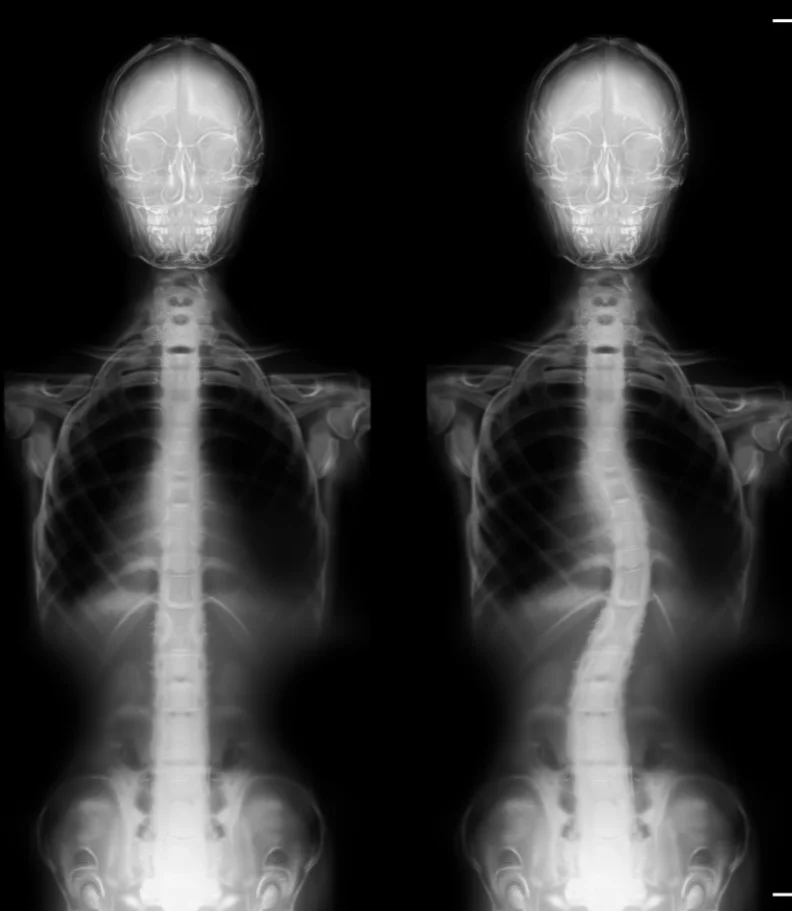

La scoliose débute généralement par une courbure subtile de la colonne vertébrale qui s’intensifie progressivement avec le temps. Un diagnostic de scoliose est posé lorsque la colonne présente une déviation de plus de dix degrés vers la droite ou la gauche lors d’un examen médical.

La scoliose se manifeste par une courbure anormale de la colonne vertébrale, s’écartant de l’alignement vertical idéal d’une colonne en bonne santé.

Si une déviation est observée, une radiographie est alors effectuée pour déterminer la gravité de la scoliose.